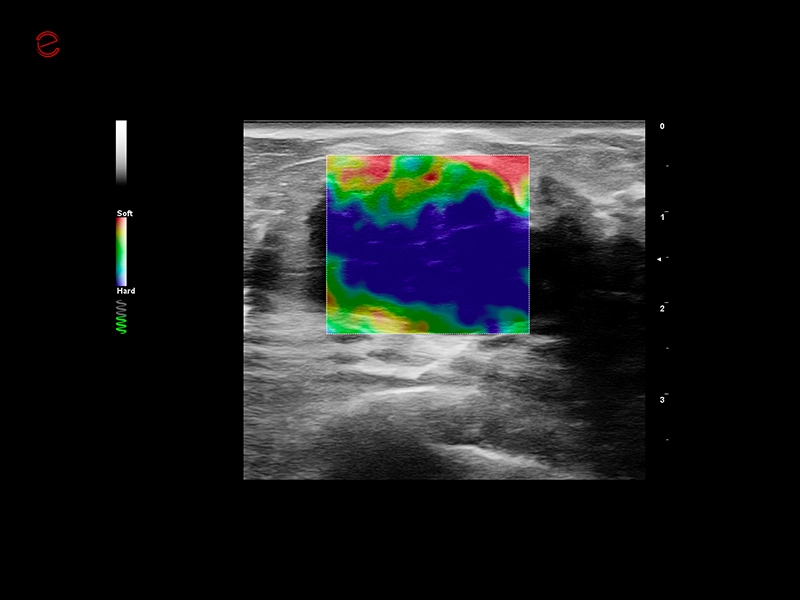

MyLab™C25 - ElaXto in breast

MyLab™C25 - ElaXto in breast